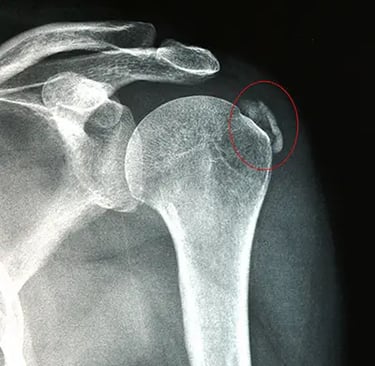

Además de la exploración física y los test diagnósticos, la ecografía nos ayuda a: localizar el depósito, valorar el estado del tendón y de los tejidos alrededor, elegir el tratamiento más adecuado y controlar la evolución.

Los síntomas pueden parecerse a otras tendinopatías o bursitis. Por eso es importante una valoración con exploración y, si procede, ecografía para confirmar el origen del dolor y elegir el tratamiento adecuado.